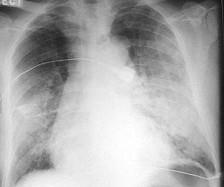

问题 男,67岁,近1个月出现活动后心悸、气短,双肺底可闻及湿性啰音,腹部检查肝脾肋下未触及,双下肢明显凹陷性水肿。胸部X线检查如图所示,超声心动图左室舒张末径61mm,左室射血分 数39%。 该病人产生双肺湿性啰音是由于 ( )

选项 A、心脏舒张功能障碍 B、心脏收缩功能障碍 C、心脏前负荷过大 D、心脏后负荷过大 E、水钠潴留

答案 B